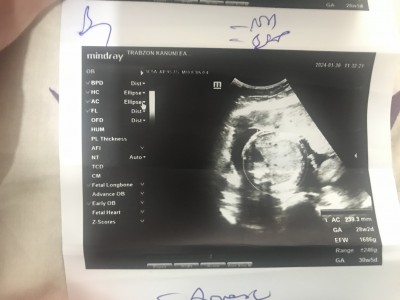

kızlar bırın de 29+1 yazıyor dıgerinde 30+1 hangisi göre gıtmem lazım acaba bide bu kağıtta 1686 cıkıyor dıger kağıtta 1230 yazıyor hangısı dogru acaba

ya benımkıde 29+5 olması lazm ama ultarsonda 30+1 yazıyor bısey anlyamdm